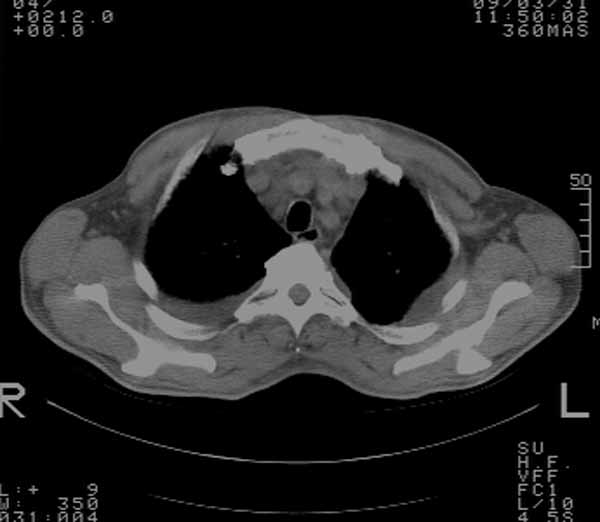

以下是引用余辉在2009-3-31 18:43:00的发言:[br]肺水肿,双侧心腔积液,心包积液,心影增大,疑似心衰

以下是引用wangyong1977在2009-3-31 20:46:00的发言:[br]肺水肿,双侧胸腔积液,心包积液,心影增大,疑似心衰 [br]

以下是引用宇宙ct在2009-3-31 18:57:00的发言:[br]肺水肿,双侧心腔积液,心包积液,心影增大,疑似心衰 [br] [br]